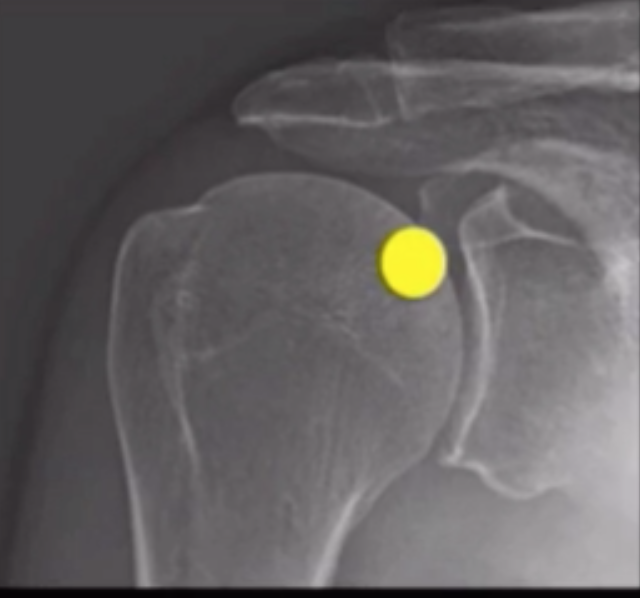

Arthrogram Shoulder

• Cocktail ~12 cc

• MRI

• 0.1 cc gadolinium

• 5 cc omnipaque

• 15 cc saline

• CT

• 8cc omnipaque

• ~8 of other shit i guess

Arthrogram

• Shoulder

• Mix contrast agents - ratio used here is

• 15 ml NS : 5 ml omnipaque : 0.1 ml gadolinium

• Position patient with arm externally rotated

• Mark target location

• Target area is upper and inner aspect of head of humerus

• Ideally should be near level of coracoid?

• Prep area

• Numb skin

• Drop needle in

• Inject contrast - look to ensure contrast is within the joint space